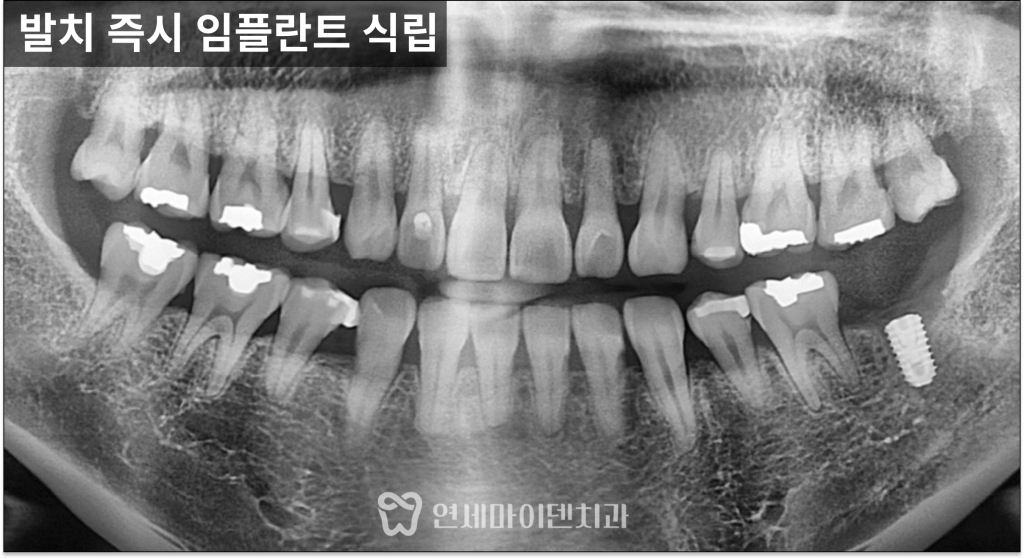

발치즉시 임플란트 증례: 어금니 흔들림

왼쪽 아래 어금니에서

냄새가 나고 흔들리는 증상으로

내원하신 케이스입니다.

발치 즉시 임플란트를 선택한 이유

임신 준비 중이라는 상황을 고려해

치료 기간을 단축하는 것이 중요했습니다.

그래서 발치와 동시에

임플란트를 식립하는

‘발치 즉시 임플란트’를 계획했습니다.